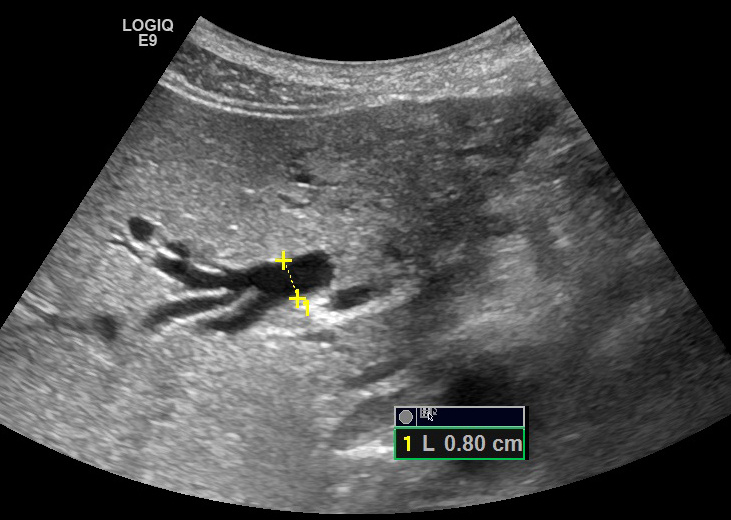

Холедох : Виден только во внутрипеченочном его отделе на очень коротком протяжении, шириной до 8 мм, далее просвет слепо обрывается, камней не видно. Складывается впечатление о перекрытии просвета холедоха эхогенным тканевым образованием (по типу опухоли Клацкина). Явного образования не выявлено, но в этой области отмечается зона изменённой структуры паренхимы печени протяженностью 36х35 мм, с крупнозернистой структурой, без четких контуров (образование?) На протяжении гепатодуоденальной связки холедох не виден, на уровне головки поджелудочной железы не виден.

Неотчетливое образование в зоне окклюзии протока